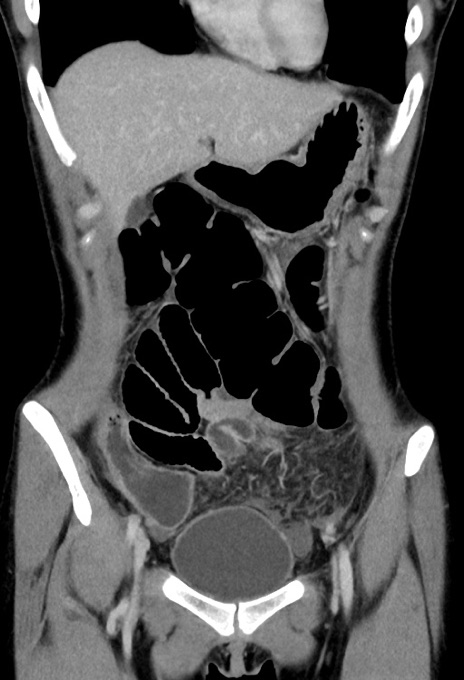

症例17(冠状断像)

【症例】20歳代女性

【主訴】嘔吐、下腹部痛

【現病歴】昨日夕食後に嘔吐し下腹部痛が出現。本日になっても嘔吐持続し改善しないため来院。

【身体所見】意識清明、BT 37.2℃、BP 108/67mmHg、腹部:平坦、やや硬、下腹部正中から右にかけて圧痛あり、反跳痛軽度あり、tapping pain(+)。

【データ】WBC 13600、CRP 14.94

横断像